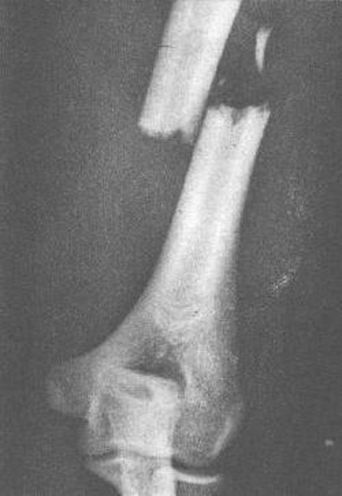

肱骨干骨折

直接暴力–横断骨折或粉碎骨折,间接暴力–斜形、螺旋形或蝶形骨折,肱骨上段的骨折–近折端向前内侧错位–远折端向上、外错位,肱骨中段骨折–近折端向外、前方移位–远折端向上移位–骨折端重叠错位。